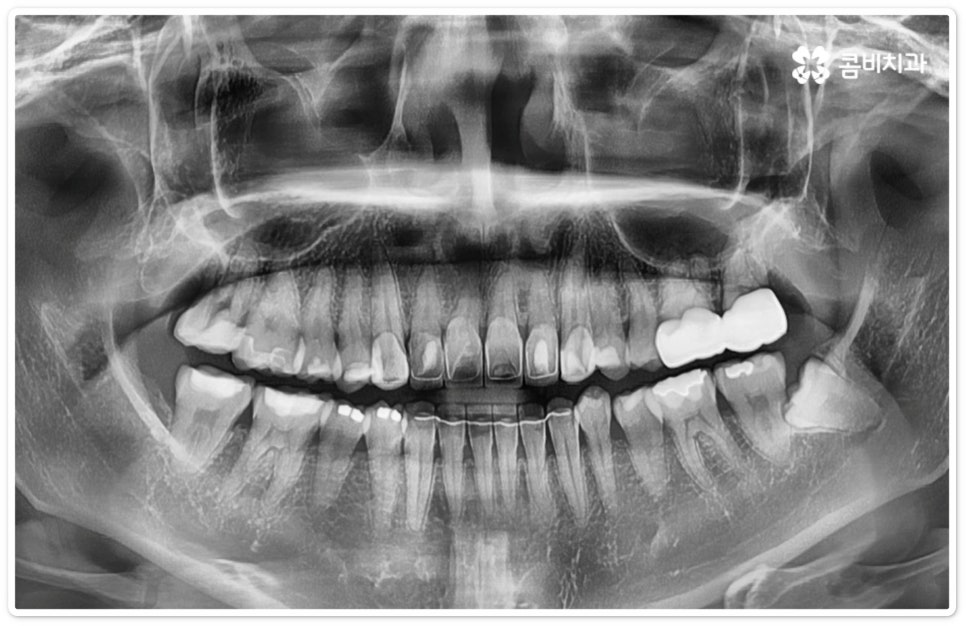

우리나라 사람 중에 약 7% 정도는 사랑니가 아예 없다고 하지만 보통 25세가 지났는데 사랑니가 나오지 않았다면 매복 사랑니이거나 누워있는 사랑니인 경우가 많으므로 정밀 검진을 받아보실 필요가 있는데요. 이때 염증을 지속적으로 유발하거나 음식물이 끼면서 관리가 잘 안 되면서 발생하는 충치 등 좋지 않은 영향을 주고 있다면 발치 처치를 해 주는 게 좋은데, 20대에 누운사랑니발치 를 진행하는 것이 40대 이후에 하는 것보다 통증 및 출혈도 덜하고 회복도 빠를 수 있으니 이를 염두에 두시길 바라고 있어요.

특히 40세 이상 성인분들의 경우 치아의 긴 뿌리가 완전하게 형성이 되어 있어 치근 유착이 심한 케이스가 있을 수 있으며 대부분 연령이 증가할수록 사랑니 주위 뼈가 단단해지고 탄력성이 감소하는 경향을 보이기 때문에 상황에 따라 무리하게 매복된 뿌리까지 발치할 경우 턱뼈가 부러지거나 신경이 손상되는 등의 합병증 위험이 증가하는 케이스에서는 치아 뿌리는 남긴 채 사랑니의 머리 부분만 잘라서 빼내는 치관절제술을 시행해야 할 수도 있는데요. 이런 경우 약 14%81%는 치관절제술 후 치아 뿌리가 상방으로 움직여서 잇몸 밖으로 노출이 되기 때문에 다시 치근을 제거하는 수술을 해주게 되는데, 환자분들의 입장에서는 수술을 두 번에 걸쳐 하기 때문에 거부감이 들 수 있으나 하치조 신경과의 거리를 벌린 후 완전히 제거하는 것이 통증 및 감염의 위험을 줄이는 보다 안전한 방법이므로 치관절제술 후 1달1년 정도의 시간을 두고 3D CT 촬영을 통해 다시 위치를 꼼꼼하게 확인한 후 치료 받으시길 권유드리고 있어요.